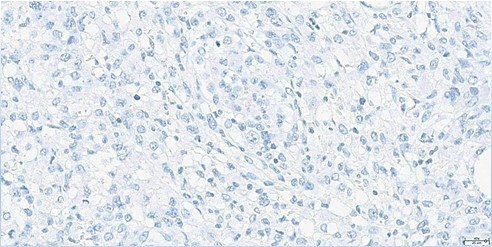

Histopathological examination revealed a non-circumscribed proliferation of large cells with marked nuclear pleomorphism, prominent nucleoli, and abundant clear cytoplasm, with numerous mitotic figures (Figure 3). Immunohistochemistry showed strong and diffuse expression of CD30 in atypical cells (Figure 4), and positivity for granzyme B, CD2, CD4, and CD25 in atypical T-cells (Figure 5). Numerous intermingled histiocytes were positive for CD68 and CD163, but negative in the atypical cells (Figures 6 and 7). ALK1 was negative in lymphoid cells (Figure 8). These findings supported the diagnosis of primary cutaneous anaplastic large cell lymphoma. Laboratory and PET-CT evaluation showed no extracutaneous disease. Localized electron beam radiotherapy was performed.

Figure 8: Immunohistochemistry for ALK1 (40x): Negative in atypical lymphoid cells.